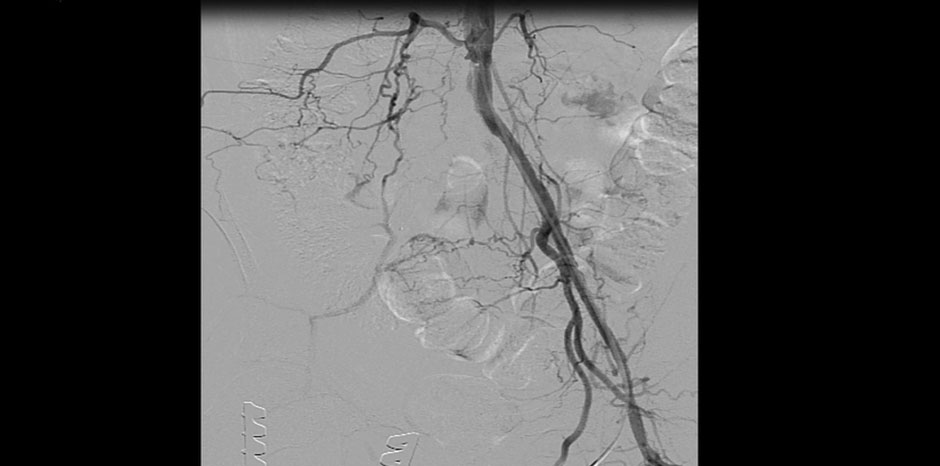

• EMBOLECTOMY BEING DONE

• BALLOONING OF STENT

• GOOD OUTFLOW IN THE END